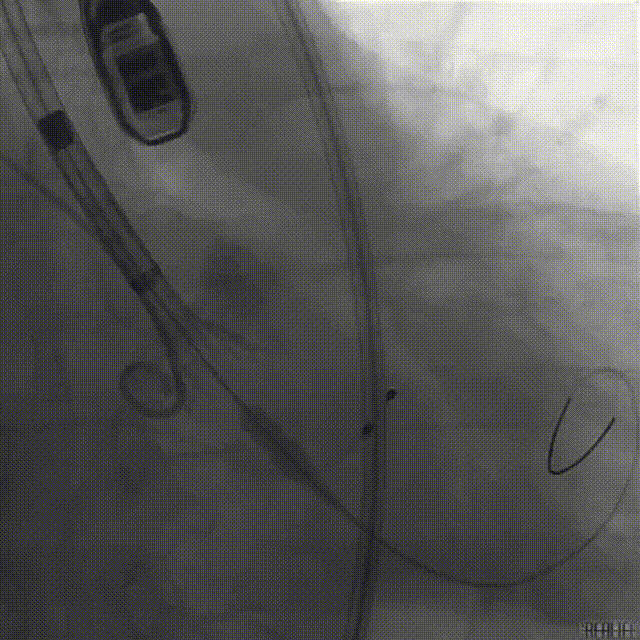

因患者自身主动脉根部结构特殊,导致定位困难:严重的钙化灶使得猪尾导管很难送至窦底;但凭借Evolut PRO稳定的多次可回收功能,术者通过对瓣膜的回收及再释放,最终找到最佳释放位置,获得最佳疗效。

瓣膜释放

评估

释放后造影

在释放过程中,手术团队严密监控各项体征,经充分评估后完全释放瓣膜。释放后评估未见冠脉阻挡,无传导阻滞,无瓣周返流,跨瓣压差由术前的160 mmHg降至10mmHg,血流动力学稳定。出导管室前即拔除气管插管,患者后自诉症状明显改善。手术获得圆满成功。